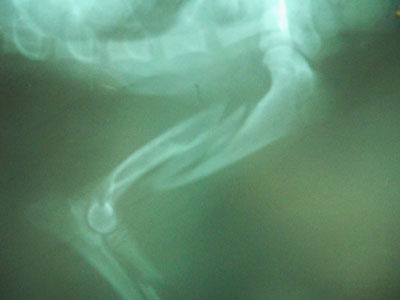

ΑΦΑΙΡΕΣΗ ΥΛΙΚΩΝ ΣΤΙΣ 19/11/2010.ΑΦΑΙΡΕΘΗΚΕ Η ΜΕΤΑΛΛΙΚΗ ΠΛΑΚΑ ΜΕ ΤΟΥΣ 7 ΚΟΧΛΙΕΣ.